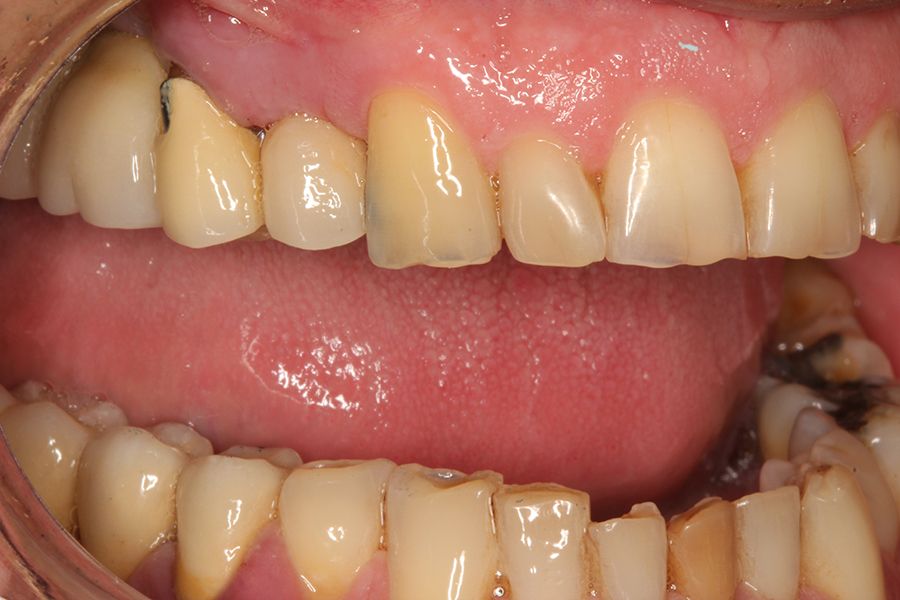

sleep disorders such as OSA and oral pathology, for example bruxism or fractures, of various rehabilitations, both on teeth and on implants, is widely documented today. This association has been demonstrated in several epidemiological studies over the years3-7, with our research group highlighting that the presence of dental wear in patients should prompt a thorough sleep analysis, as the degree of dental wear is directly related to OSA via the AHI (apnoea-hypopnoea index)9-11. This relationship is directly proportional, and it is confirmed that patients with more severe wear also exhibit a higher AHI, which is likewise associated with an increased incidence of fractures in enamel, dental roots, and prostheses. Mechanical events may,

in some cases, also affect implants, resulting in bone defects due to overload, and in extreme cases, leading to fracture of the implant itself.12-14. In the following clinical case series, we sought to retrospectively collect a group of patients who experienced adverse events in implant-supported prostheses associated with mechanical overload (fractures, loosening), to whom a subsequent polygraphic sleep study was performed, identifying those in whom these events could be related to the presence of OSA. The most severe cases identified (AHI ≥ 20) were analysed to obtain data correlating both events (OSA and mechanical complications).